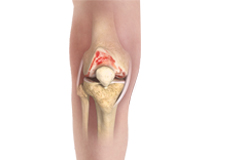

Knee Osteoarthritis

Osteoarthritis also called degenerative joint disease, is the most common form of arthritis. It occurs most often in older people. This disease affects the tissue covering the ends of bones in a joint (cartilage).In a person with osteoarthritis, the cartilage becomes damaged and worn out causing pain, swelling, stiffness and restricted movement in the affected joint.